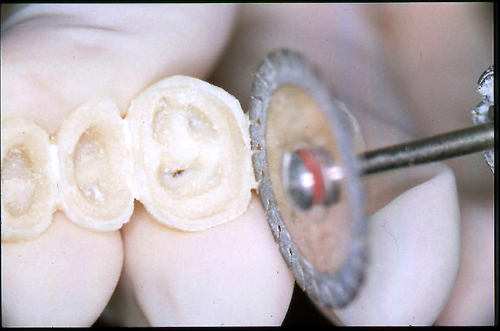

ABSTRACT El Bruxismo es una entidad patológica en la que concurren diferentes factores. Entre ellos el stress que conlleva consigo la vida moderna, constituye el Factor Predisponente sobre el que se ha abundado en innumerables tratamientos de tipo general, actuando sobre la psiquis y el comportamiento del individuo, ya sea con fármacos o bien mediante medios psicológicos. Sin embargo, como tantos desequilibrios provocados por el stress, confluyen siempre con un Factor Desencadenante, que en el caso del Bruxismo se encuentra en las desarmonías entre los componentes varios del Sistema Estomatognático. DESARROLLO Paciente varón, de 43 años, constitución atlética. A la inspección se observan desgastes oclusales que alcanzan la calidad de Facetas Parafuncionales, con dentina expuesta y empastes totalmente gastados y evidentes signos de falta de Disclusión Canina de ambos lados. Sobre dicho montaje se realiza un Encerado Progresivo de Diagnóstico, aportando en el mismo los elementos necesarios para obtener todos los principios básicos de una Oclusión Orgánica. FIG. 6 a 24 Una vez aprobado el fisiologismo de la oclusión en el articulador, se reproducen modelos de yeso con la nueva situación, y se estampa un SET UP en cada maxilar. FIG. 25/26 Procedemos entonces al tallado de las piezas correspondientes a la Guía Anterior, y rebasamos los estampados, creando en boca una nueva situación desoclusiva, que permanece en boca durante los pocos días que transcurren entre la primera y segunda visita de trabajo. FIG. 27/33 Ya abordando en esta segunda visita los sectores posteriores, tanto superiores como inferiores, tallamos siempre de manera supragingival, destacando la importancia vital de la forma obtenida en las provisionales, a las que abrimos plenamente las troneras para lograr una correcta higiene. FIG.34 a 43 FIG. 44 a 52 Efectuados los colados en oro y probados en boca, en el laboratorio se confecciona el bizcochado de la nueva Guía Anterior, la que puede o no copiarse de la Guía Anterior provisional, mediante la técnica denominada Trayectoria Funcionalmente Generada, que consiste en realizar en la platina del articulador un registro estereográfico sobre acrílico Duralay en polimerización. FIG. 57/58 Ajustados todos los detalles mediante esta técnica, se instala en boca en forma Provisional y se deja funcionando una semana o dos, al cabo de las cuales se chequean las disclusiones , los ajustes, la eficacia masticatoria, la carencia de sintomatología articular y muscular. FIG.59 a 63 PIE DE FOTO FIG.9 OBTENCIÓN DE LA GUÍA ANTERIOR FIG.10 Y 11 PITOMBOS. ALINEAC. TRIDIMENSIONAL FIG.12 PITOMBOS. DISCLUSIÓN DER. FIG.13 PITOMBOS. DISCLUSIÓN IZQ. FIG.14 WILSON INF. FIG.15 WILSON SUP. FIG.16 BOCA DE PEZ INF. FIG.17 BOCA DE PEZ SUP. FIG.18 VISTA OCLUSAL FIG.19 O.R.C. FIG.20 DISCLUSIÓN DERECHA FIG.21 CRESTAS TRIANG. INT. FIG.22 CRESTAS TRIANG. INT. FIG.23 CRESTAS TRIANG. INT. FIG 24 CRESTAS TRIANG. INT. FIG.59 DISCLUSIÓN IZQ. FIG.60 DISCLUSION IZQ. FIG.61 DISCLUSIÓN DER. FIG.62 DISCLUSION DER. FIG. 63 AJUSTE PERIFÉRICO